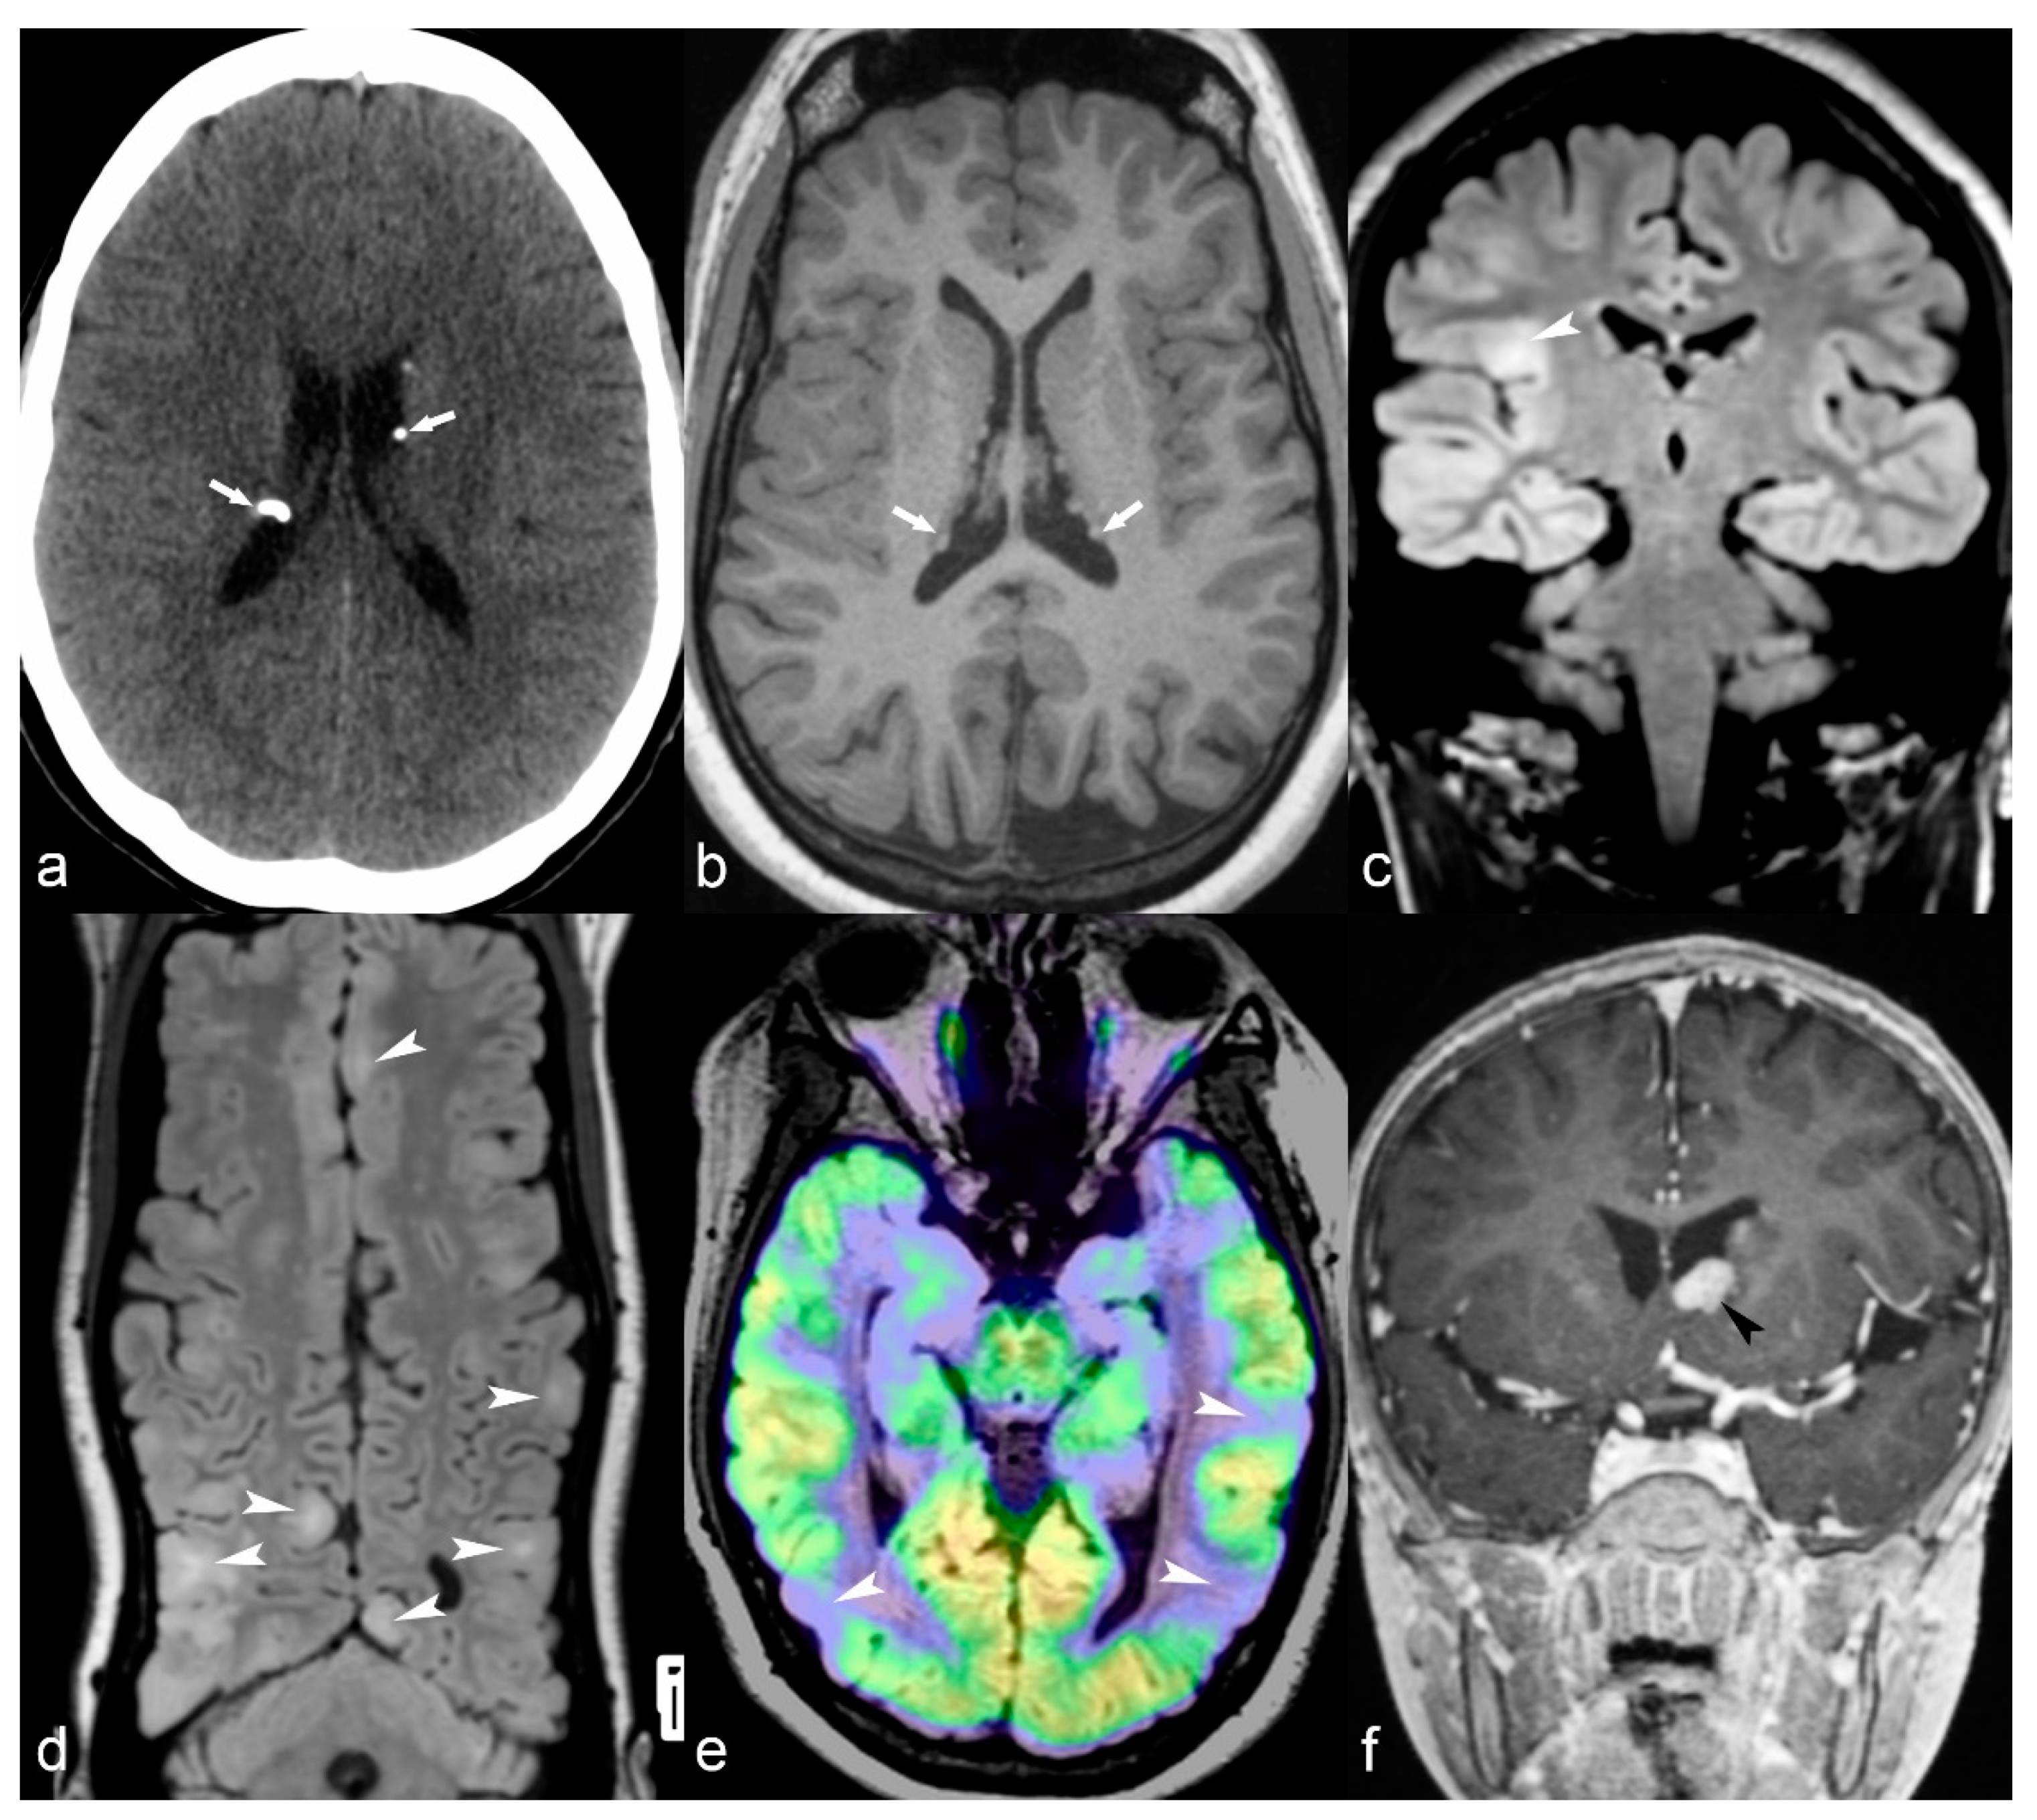

Tuberosis sclerosis complex (TSC) is a neurocutaneous syndrome usually involving the brain, skin, eyes, heart and kidneys. Brain lesions include cortical tubers, subependymal nodules, abnormal signal of white matter and subependymal giant cell astrocytomas [83]. There are different degrees of severity and clinical manifestations, but epilepsy is a common finding and usually consists of partial seizures originating in cortical tubers with presentation shortly after birth [85]. In other cases, it can be presented later in children with seizures, autistic-like behavior and mental retardation [69]. MRI readily demonstrates cortical tubers with high T2/FLAIR signal, often focally expanding the cortex (Figure 7). They usually do not enhance, but there is evidence that in case of multiple involvement, the largest tuber (usually the one that shows enhancement and hypermetabolic activity in perfusion MRI studies or PET-CT) is likely the one responsible for the seizures. Subependymal giant cell astrocytomas are grade I WHO tumors, can show enhancement and are usually located in proximity to the foramen of Monro in the lateral ventricles (Figure 7f). Subependymal nodules are periventricular or may protrude into the ventricles, may enhance or may be calcified, showing loss of signal in T2 GRE or SWI sequences or high attenuation on CT images (Figure 7a). Linear hyperintensities of white matter can also be identified in MRI studies, reflecting white matter radial migration lines [69].

Figure 7.

(a) 25-year-old female with Tuberosis Sclerosis Complex (TSC). Axial CT image (a) shows multiple calcified subependymal nodules (arrows). (b–e) Another 23-year-old female with TSC. Axial T1 weighted image (b) showing multiple subependymal hyperintense nodules (arrows). Coronal FLAIR (c) with curvilinear multiplanar reformat (d) shows multiple cortical tubers with radiating subcortical white matter hyperintensity (arrowheads). PET CT (e) shows hypometabolic areas corresponding to cortical tubers in bilateral occipito-temporal and left temporal region (arrows). (f) 14-year-old male with TSC. Coronal reformat of 3D T1 post contrast image (black arrowhead) shows enhancing subependymal giant cell astrocytoma abutting the floor of frontal horn of left lateral ventricle.